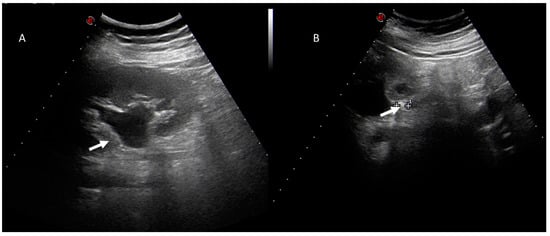

4. Clinical Setting: Abdominal Pain

6. Biliary Tract and Pancreatic Diseases

7. Ureterolithiasis